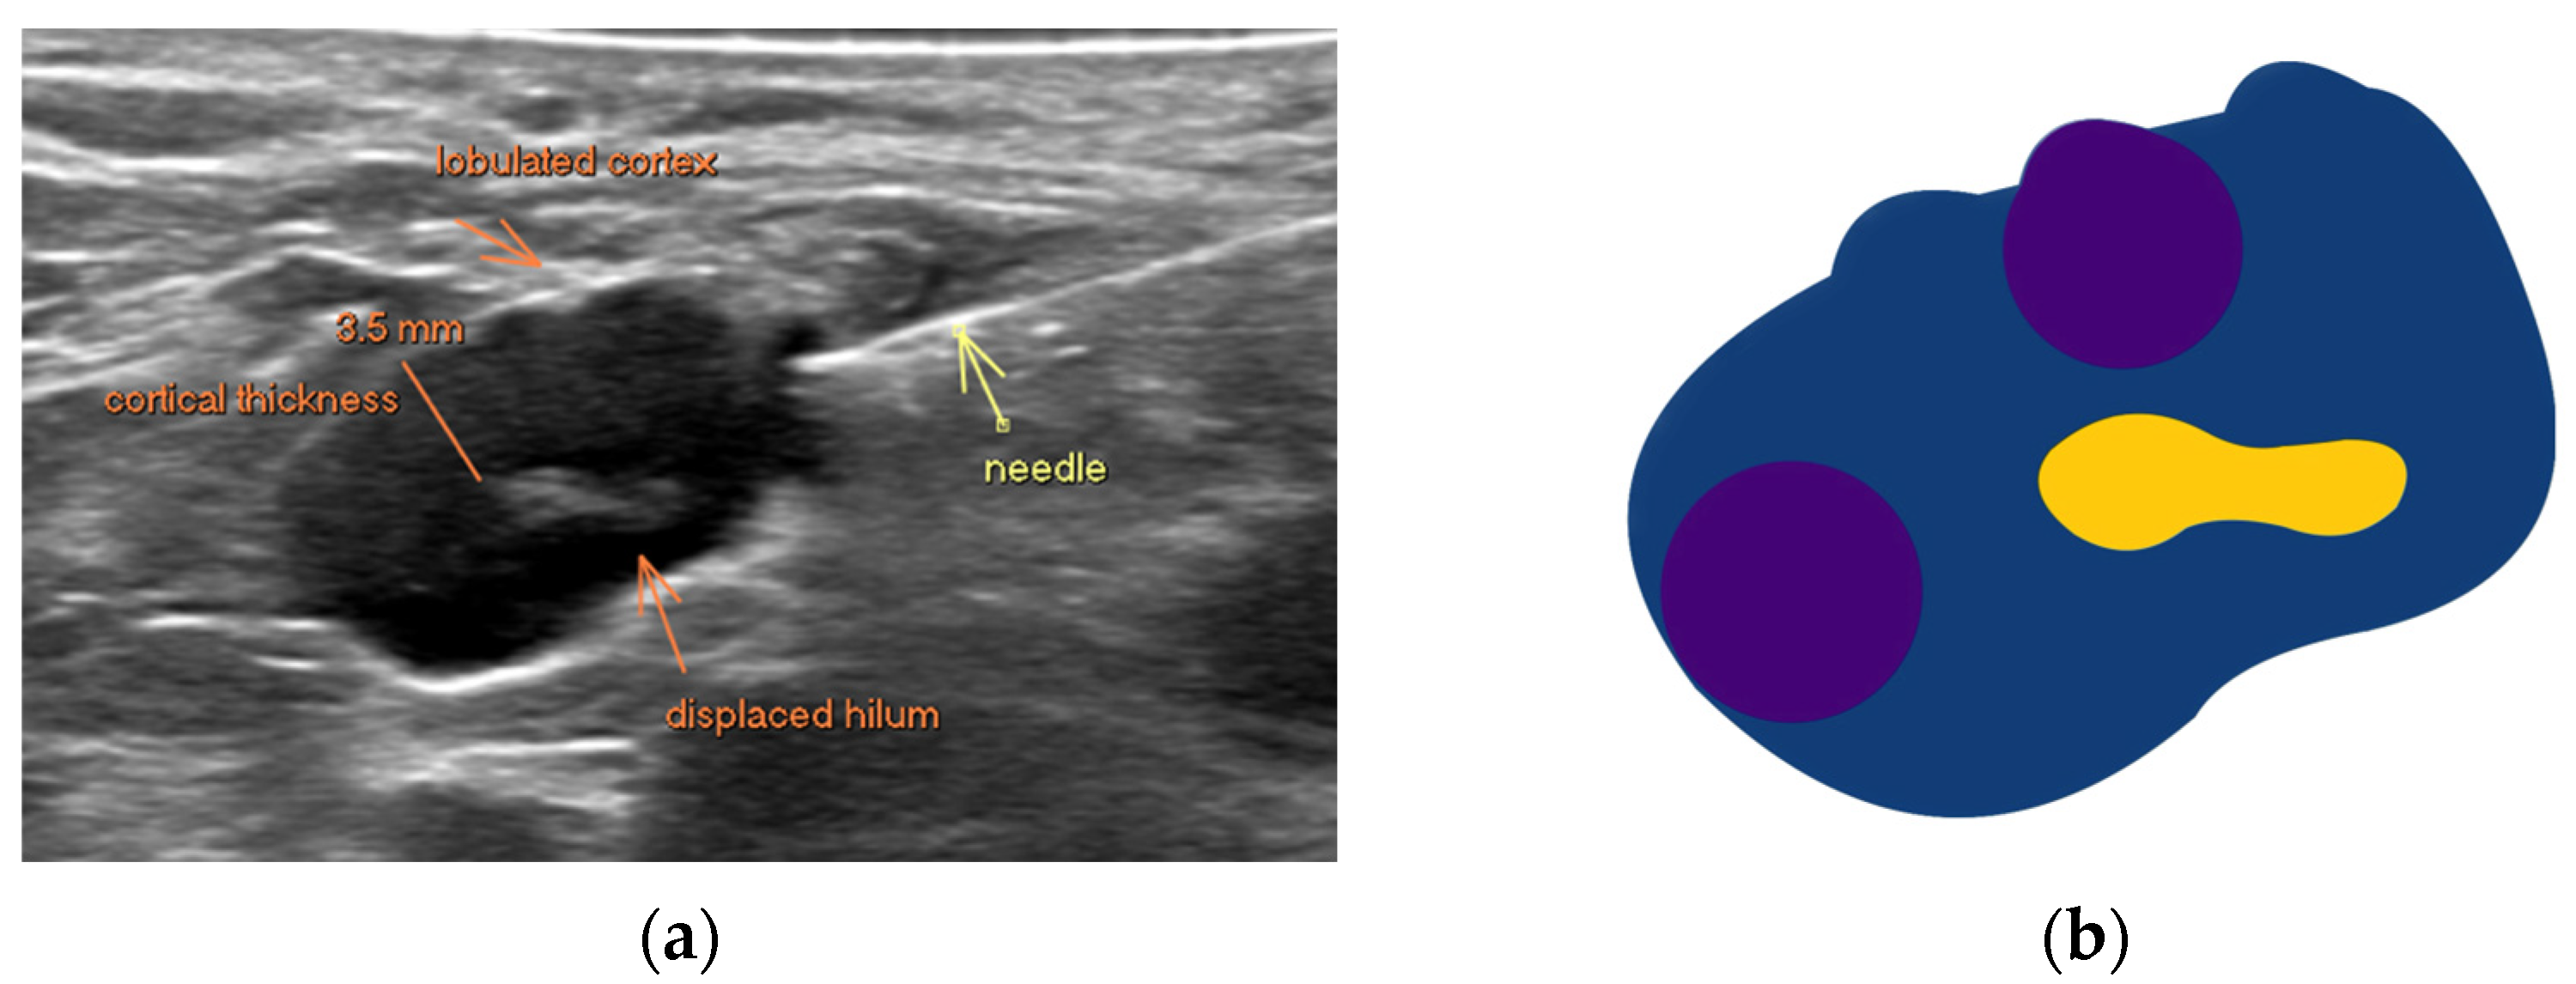

Figure 1.

(a) Ultrasound demonstrates the morphology of a suspicious axillary lymph node, confirmed malignant post-biopsy. There is diffuse cortical thickening of 3.5 mm, with a lobulated contour and displaced hilum. The needle abuts the cortex in this image. (b) Schematic representation of node with deformed displaced hilum (yellow), multilobulated cortical outline (blue) and subcapsular metastatic deposits (purple).